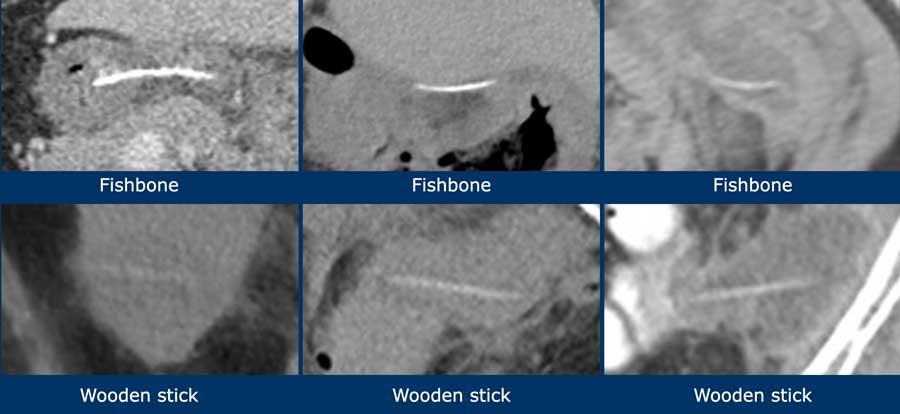

Không phải lúc nào cũng có thể phân biệt xương với que gỗ trên CT, nhưng xương cá thường tăng tỷ trọng rõ và có hình dạng cong, trong khi que gỗ ít tăng tỷ trọng hơn và có hình dạng thẳng hơn.